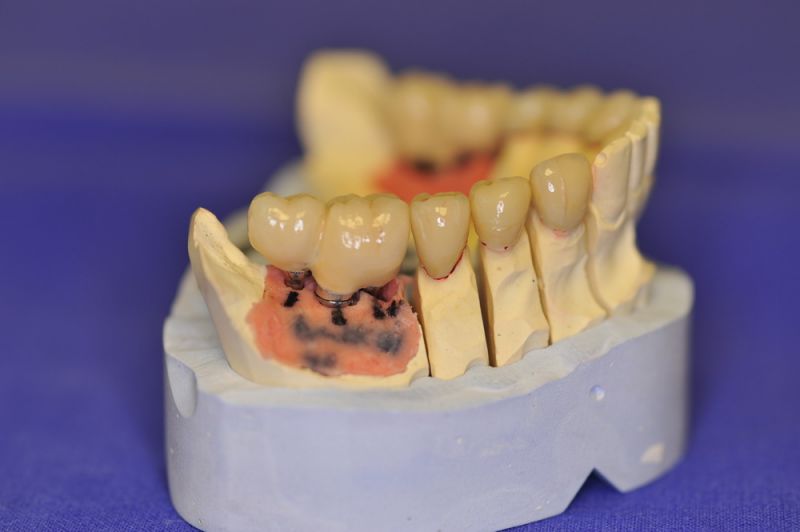

Mit dem heutigen Tag geht eine der technisch schwierigsten und anspruchsvollsten Arbeiten zu Ende, die im CMD-CENTRUM-KIEL jemals erstellt worden ist. Dabei sind es nur 10 Kronen, die benötigt werden, um die starken Kopf- und Gesichtsschmerzen der Patienten zu beseitigen.

Die Lösung einer Vielzahl technischer Probleme, die vorrangig verursacht waren durch:

4. Notwendigkeit die Mundhygienefähigkeit der Arbeit auch unter sehr beengten Verhältnissen zu schaffen, um der Arbeit eine günstige Prognose mitzugeben.